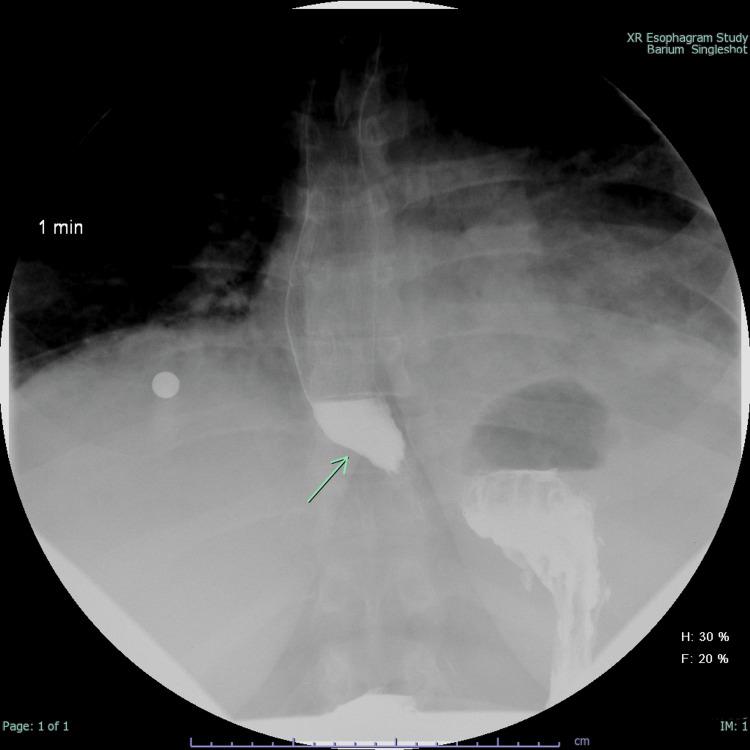

Myositis is a group of rare autoimmune disorders characterized by chronic inflammation of skeletal muscles that leads to a hallmark triad of muscle weakness, fatigue, and myalgia. Extra-muscular manifestations are sometimes seen and involve various organ systems, including the gastrointestinal (GI) tract. In this case series, two patients with polymyositis (PM) and dermatomyositis (DM), both of whom developed dysphagia as a complication of myositis, are discussed. Case 1 was a female with a known history of biopsy-proven dermatomyositis who presented with progressive peripheral edema and weakness affecting all extremities. Concurrently, she displayed symptoms of pneumonia and dysphagia associated with frequent spontaneous or self-induced vomiting to alleviate retrosternal discomfort. Esophagogastroduodenoscopy (EGD) revealed esophageal dilatation and an absence of a contractile response, consistent with myositis. Treatment comprised intravenous immunoglobulin (IVIG), mycophenolate, and lifestyle modifications, including dietary adjustments and maintaining an upright position postprandial. The second case was a female with muscle weakness and dysphagia. Video-fluoroscopic swallow assessment was significant for pharyngeal dysfunction without a sensory response to penetrated material, and the patient was at high risk of aspiration with any oral intake. The presence of pharyngeal dysfunction and dysphagia prompted treatment with IVIG, mycophenolate, and percutaneous endoscopic gastrostomy (PEG) tube placement. These cases have highlighted the upper GI complications observed in patients with myositis, accentuating the necessity for a personalized treatment approach. Timely intervention has shown promising results in symptomatic relief and improving patient outcomes. This emphasizes the importance of a multidisciplinary approach when addressing myositis-related upper GI manifestations.

肌炎是一组罕见的自身免疫性疾病,其特征是骨骼肌的慢性炎症,导致肌肉无力、疲劳和肌痛这一典型三联征。有时会出现肌肉外表现,累及包括胃肠道(GI)在内的各种器官系统。在本病例系列中,讨论了两名患有多发性肌炎(PM)和皮肌炎(DM)的患者,他们均因肌炎并发症出现吞咽困难。病例1是一名女性,有活检证实的皮肌炎病史,表现为进行性外周水肿和累及所有肢体的无力。同时,她出现肺炎症状以及吞咽困难,伴有频繁的自发或自我诱发呕吐以缓解胸骨后不适。食管胃十二指肠镜检查(EGD)显示食管扩张且无收缩反应,符合肌炎表现。治疗包括静脉注射免疫球蛋白(IVIG)、霉酚酸酯以及生活方式调整,包括饮食调整和餐后保持直立姿势。第二个病例是一名有肌肉无力和吞咽困难的女性。视频荧光吞咽评估显示存在咽部功能障碍,对穿透物质无感觉反应,患者经口摄入任何食物均有高误吸风险。咽部功能障碍和吞咽困难的存在促使采用IVIG、霉酚酸酯治疗以及经皮内镜下胃造口术(PEG)置管。这些病例突出了肌炎患者中观察到的上消化道并发症,强调了个性化治疗方法的必要性。及时干预在缓解症状和改善患者预后方面已显示出有希望的结果。这强调了在处理与肌炎相关的上消化道表现时采用多学科方法的重要性。